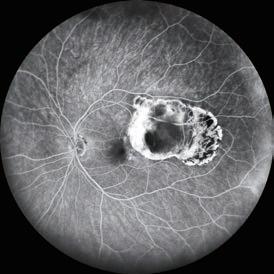

In addition to MMP-9, levels of other pro-inflammatory markers increased progressively across the three “control groups”, were significantly greater in the subclinical inflammation I and II groups compared to controls with no inflammation, and were almost identical in the subclinical inflammation II and DED cohorts.

The testing, sample preparation, and platform processing take 90 minutes. In addition to MMP-9, the test measures levels of four pro-inflammatory cytokines (interleukin [IL]-1β, IL-6, IL-17A, TNF-α), VEGF, soluble ICAM-1, and IL-10, an antiinflammatory cytokine included to help understand the balance between pro- and anti-inflammatory factors, Dr Shirodkar said.

None of the study groups had elevated levels of IL-10 or VEGF, Dr Shirodkar reported.

The system uses a customised ELISA platform (Bio-M Pathfinder) to measure eight soluble factors in tear fluid extracted from Schirmer’s strips. The developers conducted a study that included 107 patients with DED diagnosed per TFOS DEWS II guidelines, 125 patients with keratoconus, and 389 controls scheduled for refractive surgery who had no overt signs of DED. The controls were further stratified into three groups based on matrix metalloproteinase-9 (MMP-9) level: no inflammation <50,000 pg/mL (n=214); subclinical inflammation I 50,000 to 162,000 pg/mL (n=95); and subclinical inflammation II >162,000 pg/mL (n=80).

Currently, the researchers are generating additional data sets to improve the robustness of the analysis and are adding to the keratoconus cohort to hopefully identify grade-specific differences and progression-related changes.

“We hope to popularise our concept of targeted therapy for DED that uses a biomarker-based algorithm to rationalise the manner in which we deliver care to these patients,” Dr Shirodkar said.

EUROTIMES | SEPTEMBER 2022